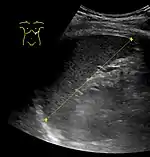

![]() | |

| CT scan in a patient with chronic lymphocytic leukemia, showing splenomegaly. Yellow arrows point at the spleen. | |